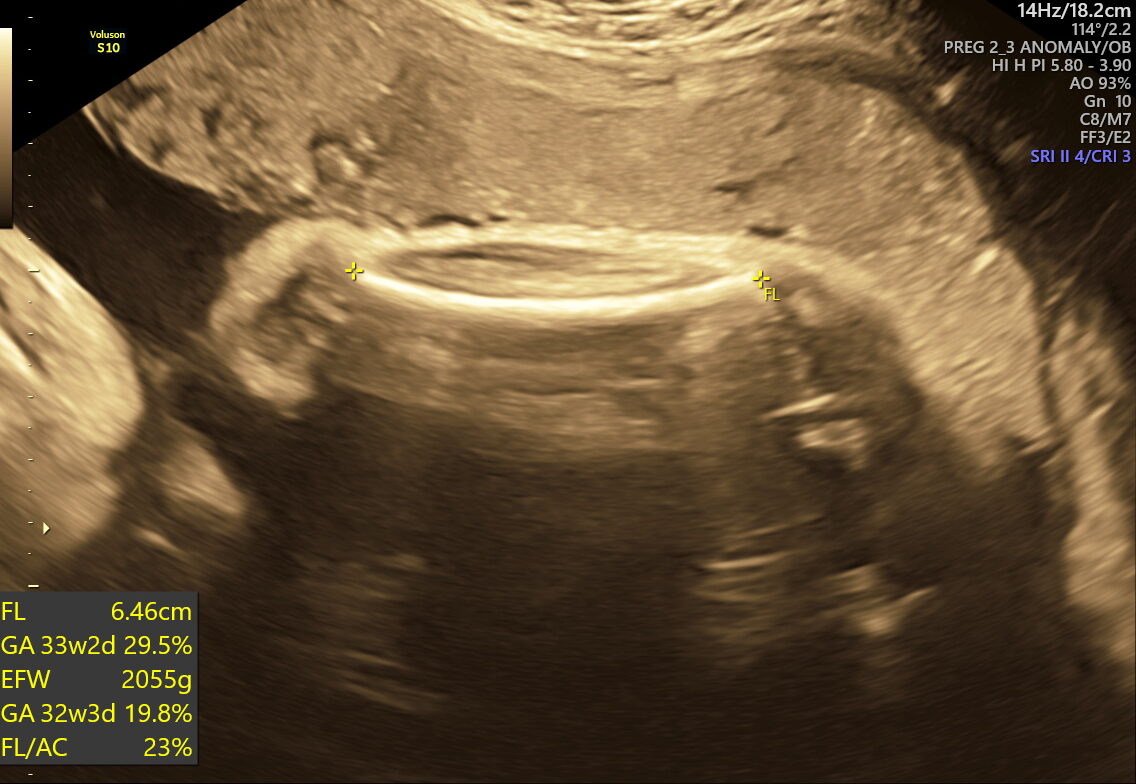

- Fetal Growth & Weight: Verifies if your baby’s size and weight meet healthy expectations for their gestational age.

This scan focuses on confirming birth readiness and spotting sudden issues that may arise close to your due date. It includes detailed Doppler studies to check blood flow in the umbilical cord and brain, ensuring your baby gets enough oxygen and nutrients.

While often recommended for at-risk pregnancies, NESA specialists may advise it for all expecting parents seeking peace of mind and a smooth delivery. Research shows that a routine well-being ultrasound in third trimester is highly effective for detecting growth restrictions that may affect outcomes for mothers and babies.

- Fetal Growth Restriction (FGR) or macrosomia (large baby)